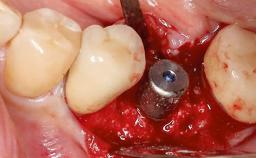

Paolo Casentini demonstrates that peri-implantitis can be successfully treated even at an advanced stage. He discusses a case in which the existing implants and prostheses were both retained while regenerating the defect and creating a band of keratinized tissue. A 69-year-old female patient was referred by her general dentist for evaluation of a recurrent infection at previously placed and restored implants in the posterior left mandible. The patient’s chief complaint was recurrent swelling and pain in the molar region of the left posterior mandible with discomfort during brushing in the same area. The patient reported receiving two implants (36 and 37) nine years earlier.